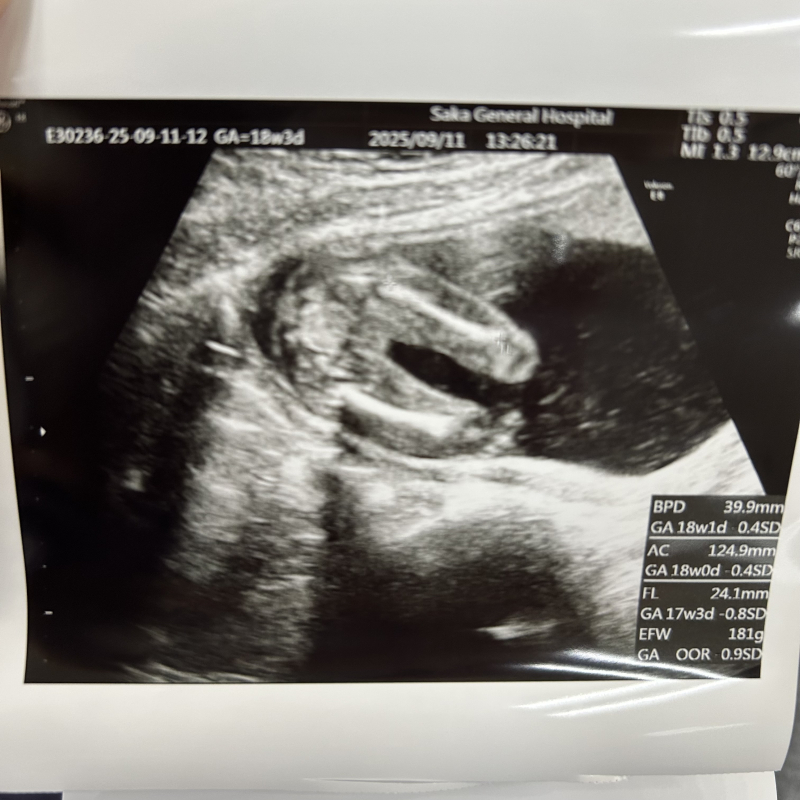

18週3日のエコーで女の子か男の子か判断してほしいです🍀♡

先生には女の子って言われました♪

女の子なら木の葉屋コーヒー豆と言われる部分は写っているかも教えてほしいです!

こちらでは、超音波検査の診断はしない決まりになっていますが、おちんちんが見えないので医師のいう通り女の子の可能性が高いかと思います。おんなのこの陰唇部分は確認できませんでした。